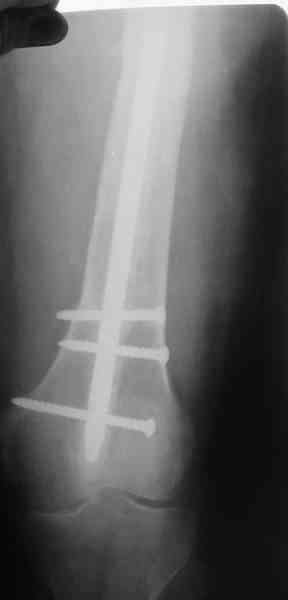

1, 2, 3, 4 - рентгенограммы бедра от 8 августа этого года (через четыре месяца после операции);

В качестве демонстрации лечения канального остеомиелита бедренной кости представляем пациентку (см. parts 2 и 3), которая как раз сегодня была у нас на контрольном осмотре. В мае этого года мы произвели ей фиксацию бедренной кости штифтом-спейсером по поводу ложного сустава и канального остеомиелита бедренной кости. Через 4 недели после операции свищи закрылись. Сейчас она ходит с полной нагрузкой на конечность.

4, 5, 6 - рентгенограммы бедра и фотографии пациентки (прошу прощения за низкое качество рентгеновских снимков) от 7 сентября 2007 г.